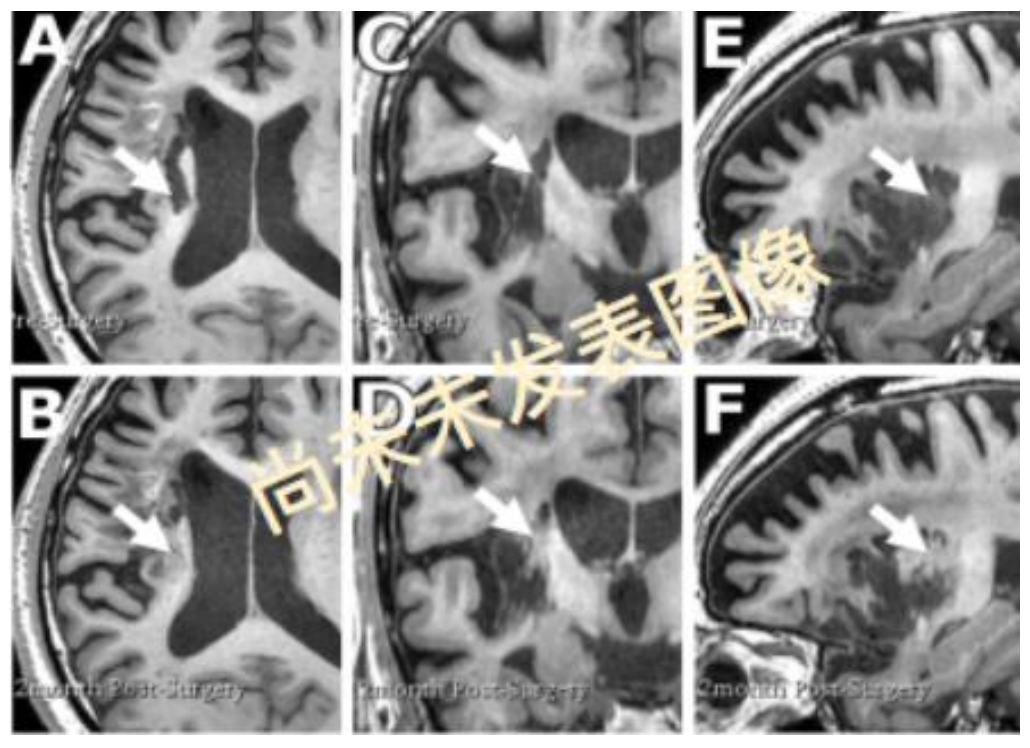

直观的核磁图像新生组织生长

发现梗塞灶内移植后12个月与基线比较出现新生组织,发生脑结构改变(A,C,E为基线期,B,D,F为移植后12个月,A,B为轴位, C,D为冠状位,E,F为矢状位)